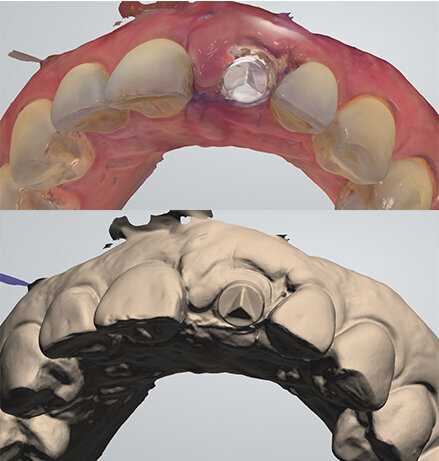

Intraoral scan

Eight days after surgery, the patient reported that healing was uneventful and the prosthodontist removed the stitches. It has become the author’s standard protocol to perform an intraoral scan for implant position in this same session (Figs. 24 & 25). The specific and unique PEEK healing abutment used has an internal circular channel and on one side, normally positioned on the buccal aspect, a vertical rectangular slot (Fig. 26). After removing the PTFE tape used to plug this area during surgery, a ScanPeg can be positioned inside the healing abutment. This allows for a unique scanning procedure without removing the healing abutment, thus avoiding disturbing healing tissue or dislocating recently placed biomaterials. The producer provides libraries for STL files of the five different anatomical shapes—wide incisor, narrow incisor, canine, premolar and molar—that determine the basic profile of the gingival tunnel during healing.